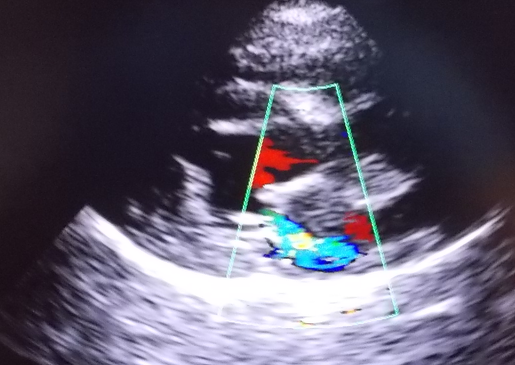

心臓のエコー検査では、僧帽弁が厚くビロビロになって閉鎖不全が生じているため、左心室から左心房の方に逆流する血流(青いところ)が認められます。この子は1日程度、酸素テント(ICU装置)で入院しながら、心臓の点滴を行うことで、心原性肺水腫が改善し、現在は内服薬で普段の生活に支障がない状態で管理できています。(5ヶ月後のレントゲン写真で肺水腫が改善し、心臓の肥大も改善しているのがわかります)